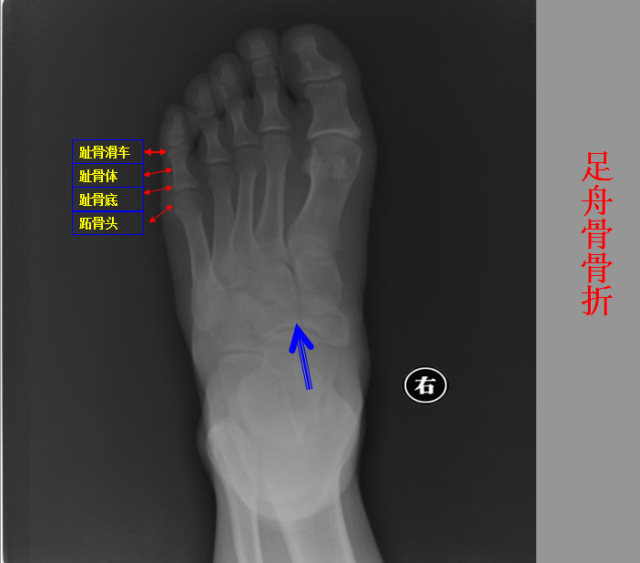

收藏!放射科急诊夜班时可能会遇到的100张图像

骨折篇

定义:骨折{Fracture}是指骨的完整性和连续性的折裂或粉碎。包括创伤性骨折、疲劳性骨折和病例理性骨折。 临床上以创伤性骨折*常见。